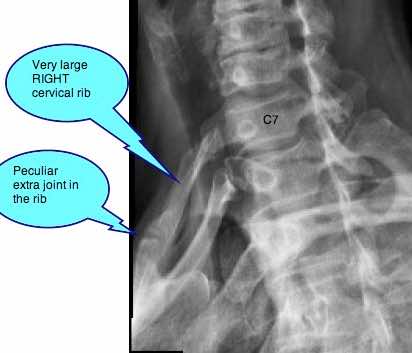

Originating from the C7 transverse process and passing through the interscalene triangle, this extra rib can severely interfere with the normal function of the arm.

In most instances cervical ribs are small structures of little clinical significance. However, very occasionally, they may be enormous influencing either the subclavian artery or the brachial plexus of nerves, or both.

On the right, for the first time in my whole clinical life, I could detect absolutely no radial pulse; zilch. So it was impossible to do Adson's test which is dependent on a normal radial pulse.

I ordered new X-rays.